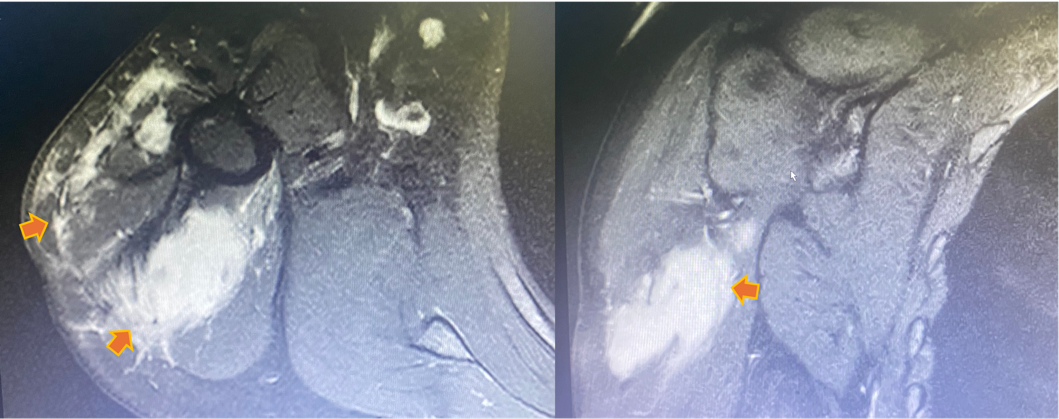

图1 右上臂肌间隙内多发软组织占位

刘女士曾多次外院就诊但症状依旧没有缓解,软组织肿物多次复发。经多方打听,遂来到广东省河源市人民医院就诊。关节外科和运动医学科曾红生主任领导的骨肿瘤诊疗团队经全面的专科检查后发现,刘女士右上臂病灶为右上臂肌间隙内多发占位性病变,病理诊断为结节性筋膜炎,难点在于患者已进行了两次手术,目前复发的病灶缺乏明确的边界,肿瘤与臂丛神经血管束粘连紧密。针对患者的复杂情况,省医专家黄文汉医生主持了全科术前讨论,制定了缜密的术前规划设计,认为本次手术的风险及难点在于肿瘤范围较大,为完整切除肿瘤须进行扩大范围的肿瘤切除术尽量达到R0切除;结节性筋膜炎是良性侵袭性肿瘤,易复发是处理难点,如何尽量在保留上肢功能的情况下保留神经血管束,消除微卫星病灶,消灭术腔残留病灶从而减少肿瘤原位复发是难点。经过全科细致的讨论,决定为患者施行右上臂病损扩大切除术+臂丛神经血管探查松解术+创面负压吸引术。